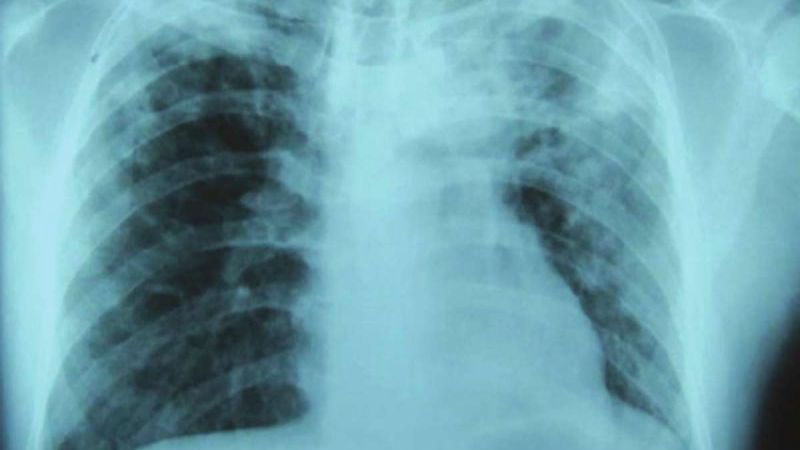

La enfermedad es causada por una bacteria que a menudo infecta los pulmones y es altamente transmisible cuando los enfermos tosen o estornudan. Aproximadamente una cuarta parte de la población mundial tiene una infección de tuberculosis latente, lo que significa que son portadores de la bacteria, pero no se han enfermado y no pueden transmitirla. Aquellos que albergan la bacteria tienen entre 5 y 10% de posibilidades de desarrollar tuberculosis.